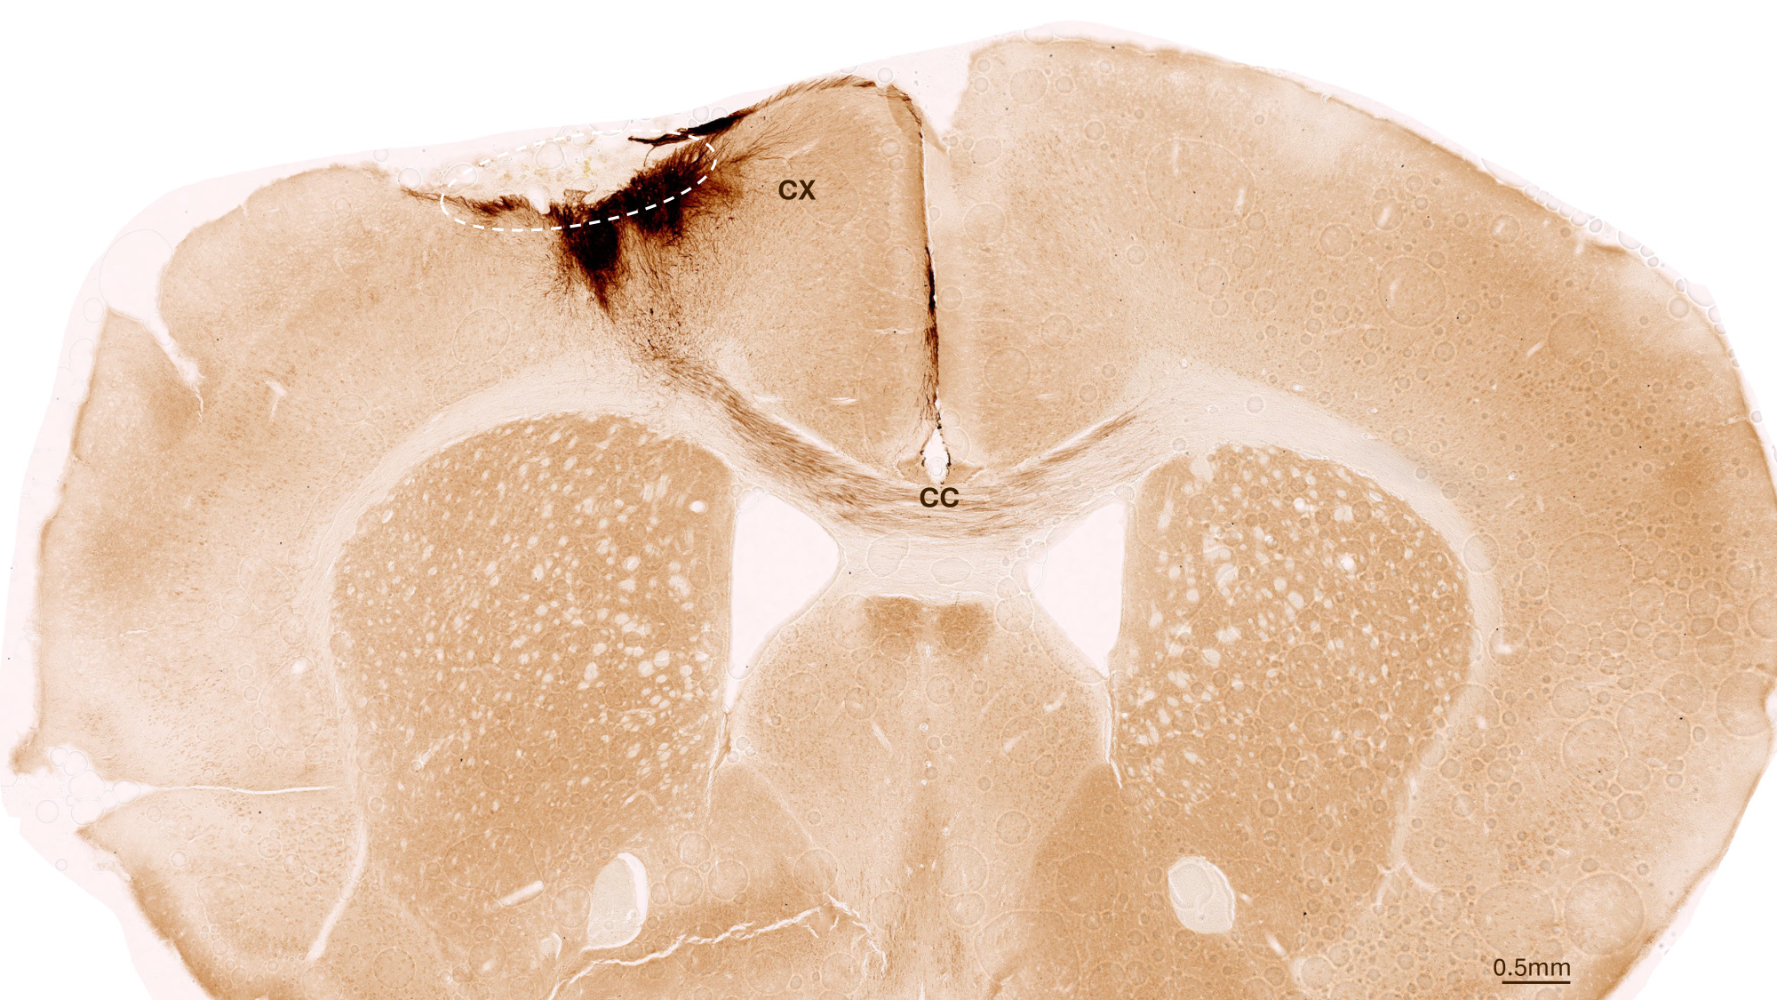

Eine Woche nach dem Schlaganfall transplantierte das Team neuronale Stammzellen in die betroffenen Hirnregionen und beobachtete die Entwicklung mit einer Vielzahl an bildgebenden und biochemischen Methoden. «Es zeigte sich, dass die Stammzellen den gesamten Analysezeitraum von fünf Wochen überlebten und sich grösstenteils zu Nervenzellen umbildeten − die sogar mit den bereits vorhandenen Hirnzellen kommunizierten», sagt Tackenberg.